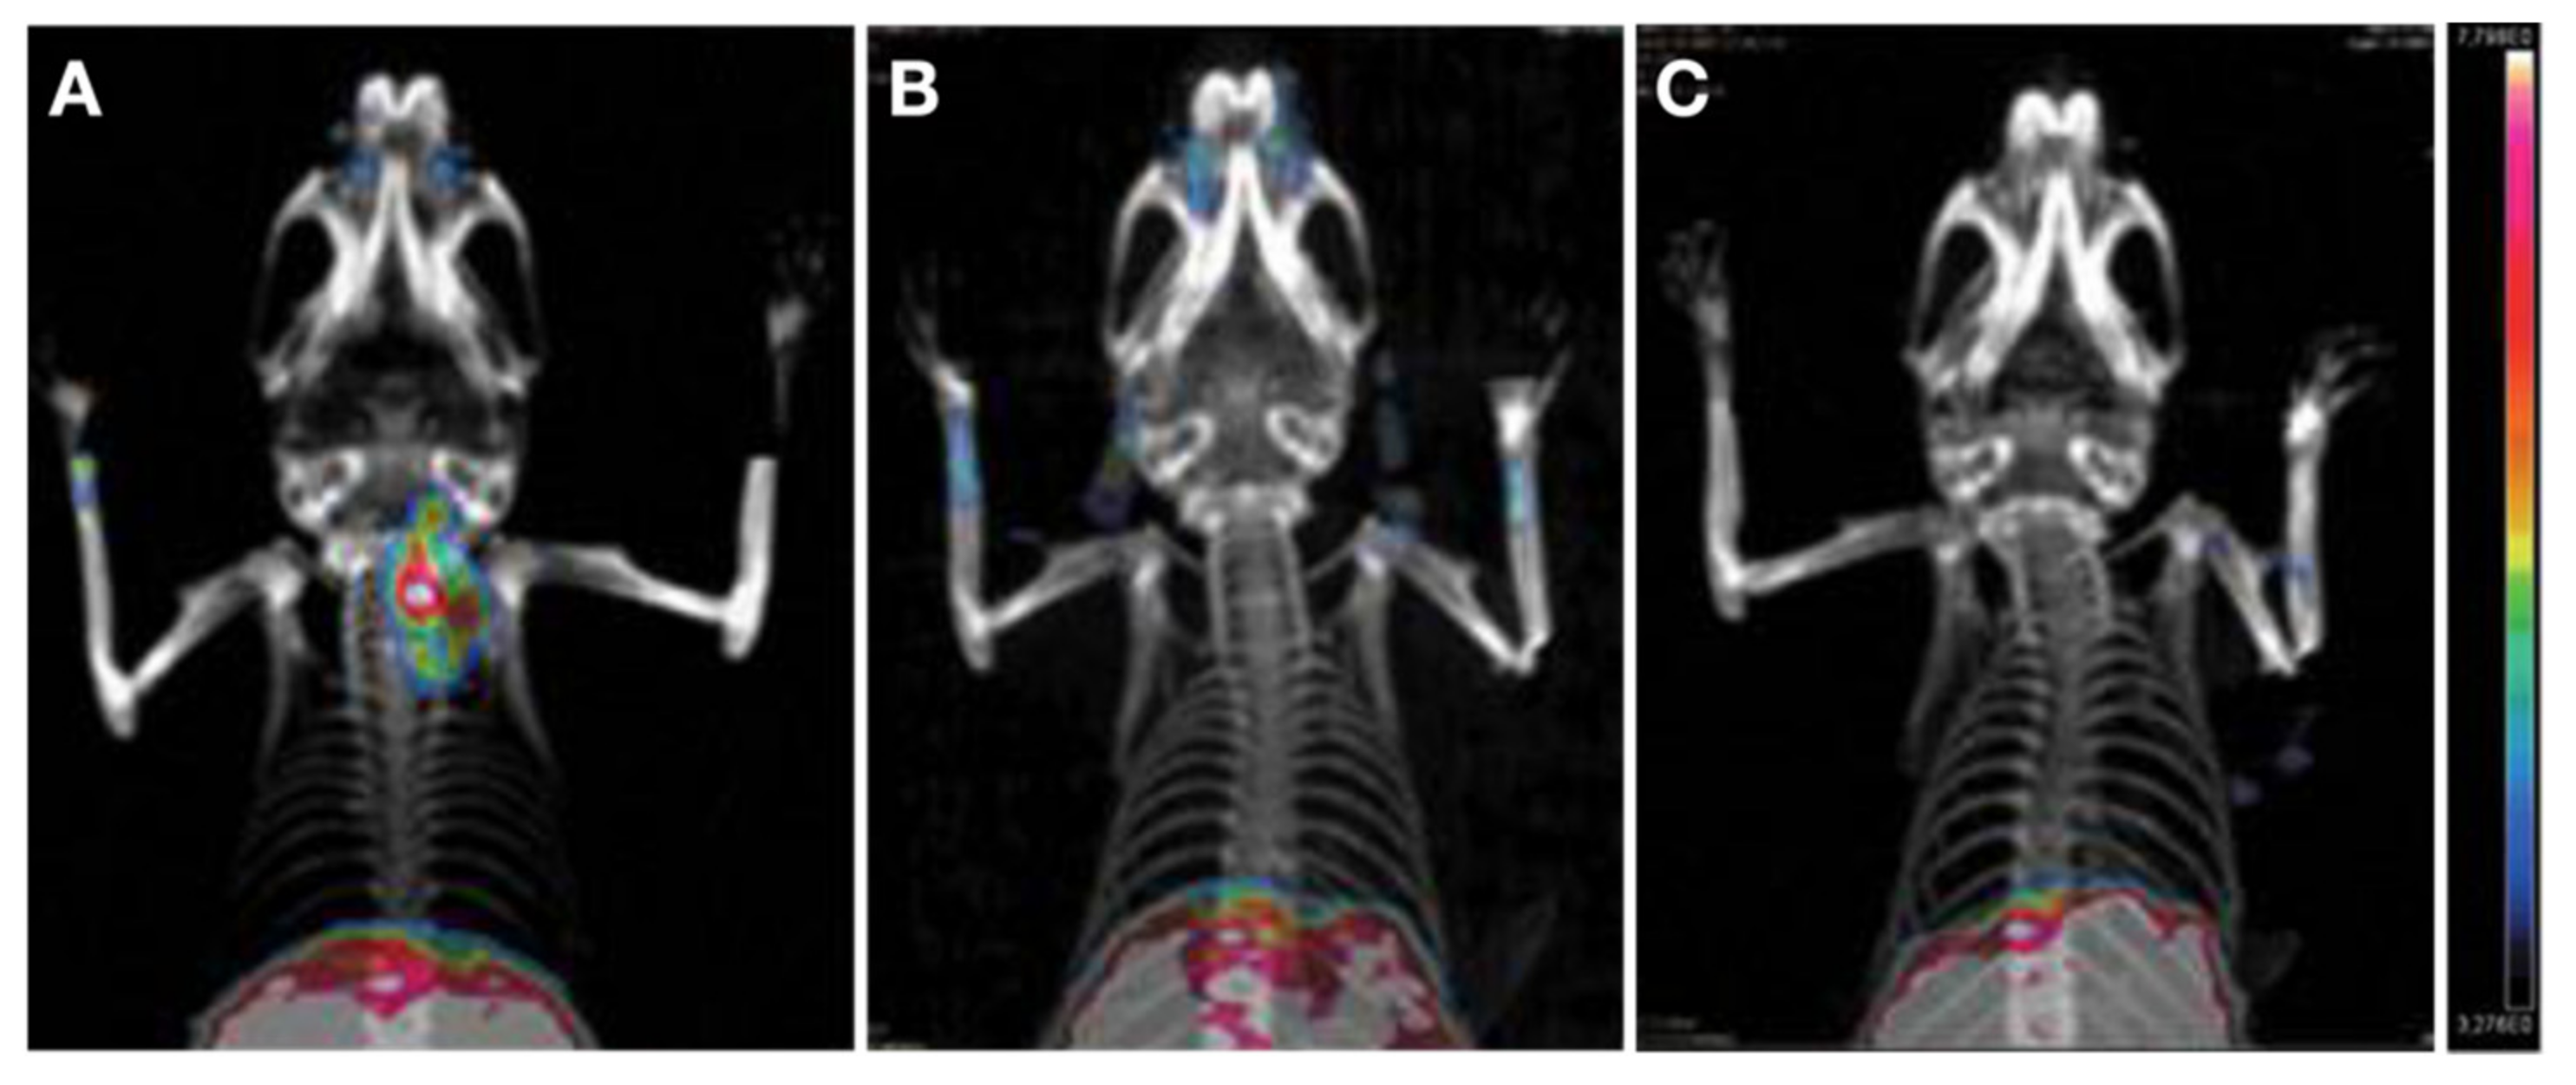

- Wei, W.; Jiang, D.; Rosenkrans, Z.T.; Barnhart, T.E.; Engle, J.W.; Luo, Q.; Cai, W. HER2-Targeted Multimodal Imaging of Anaplastic Thyroid Cancer. Am. J. Cancer Res. 2019, 9, 2413–2427. [Google Scholar]